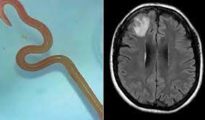

Denuncian una contaminación potencialmente dañina para la salud de la vacuna Pfizer contra el covid

Agustina Sucri .- Alguien debería forzar a que se secuencien muestras de ADN de personas vacunadas contra el…